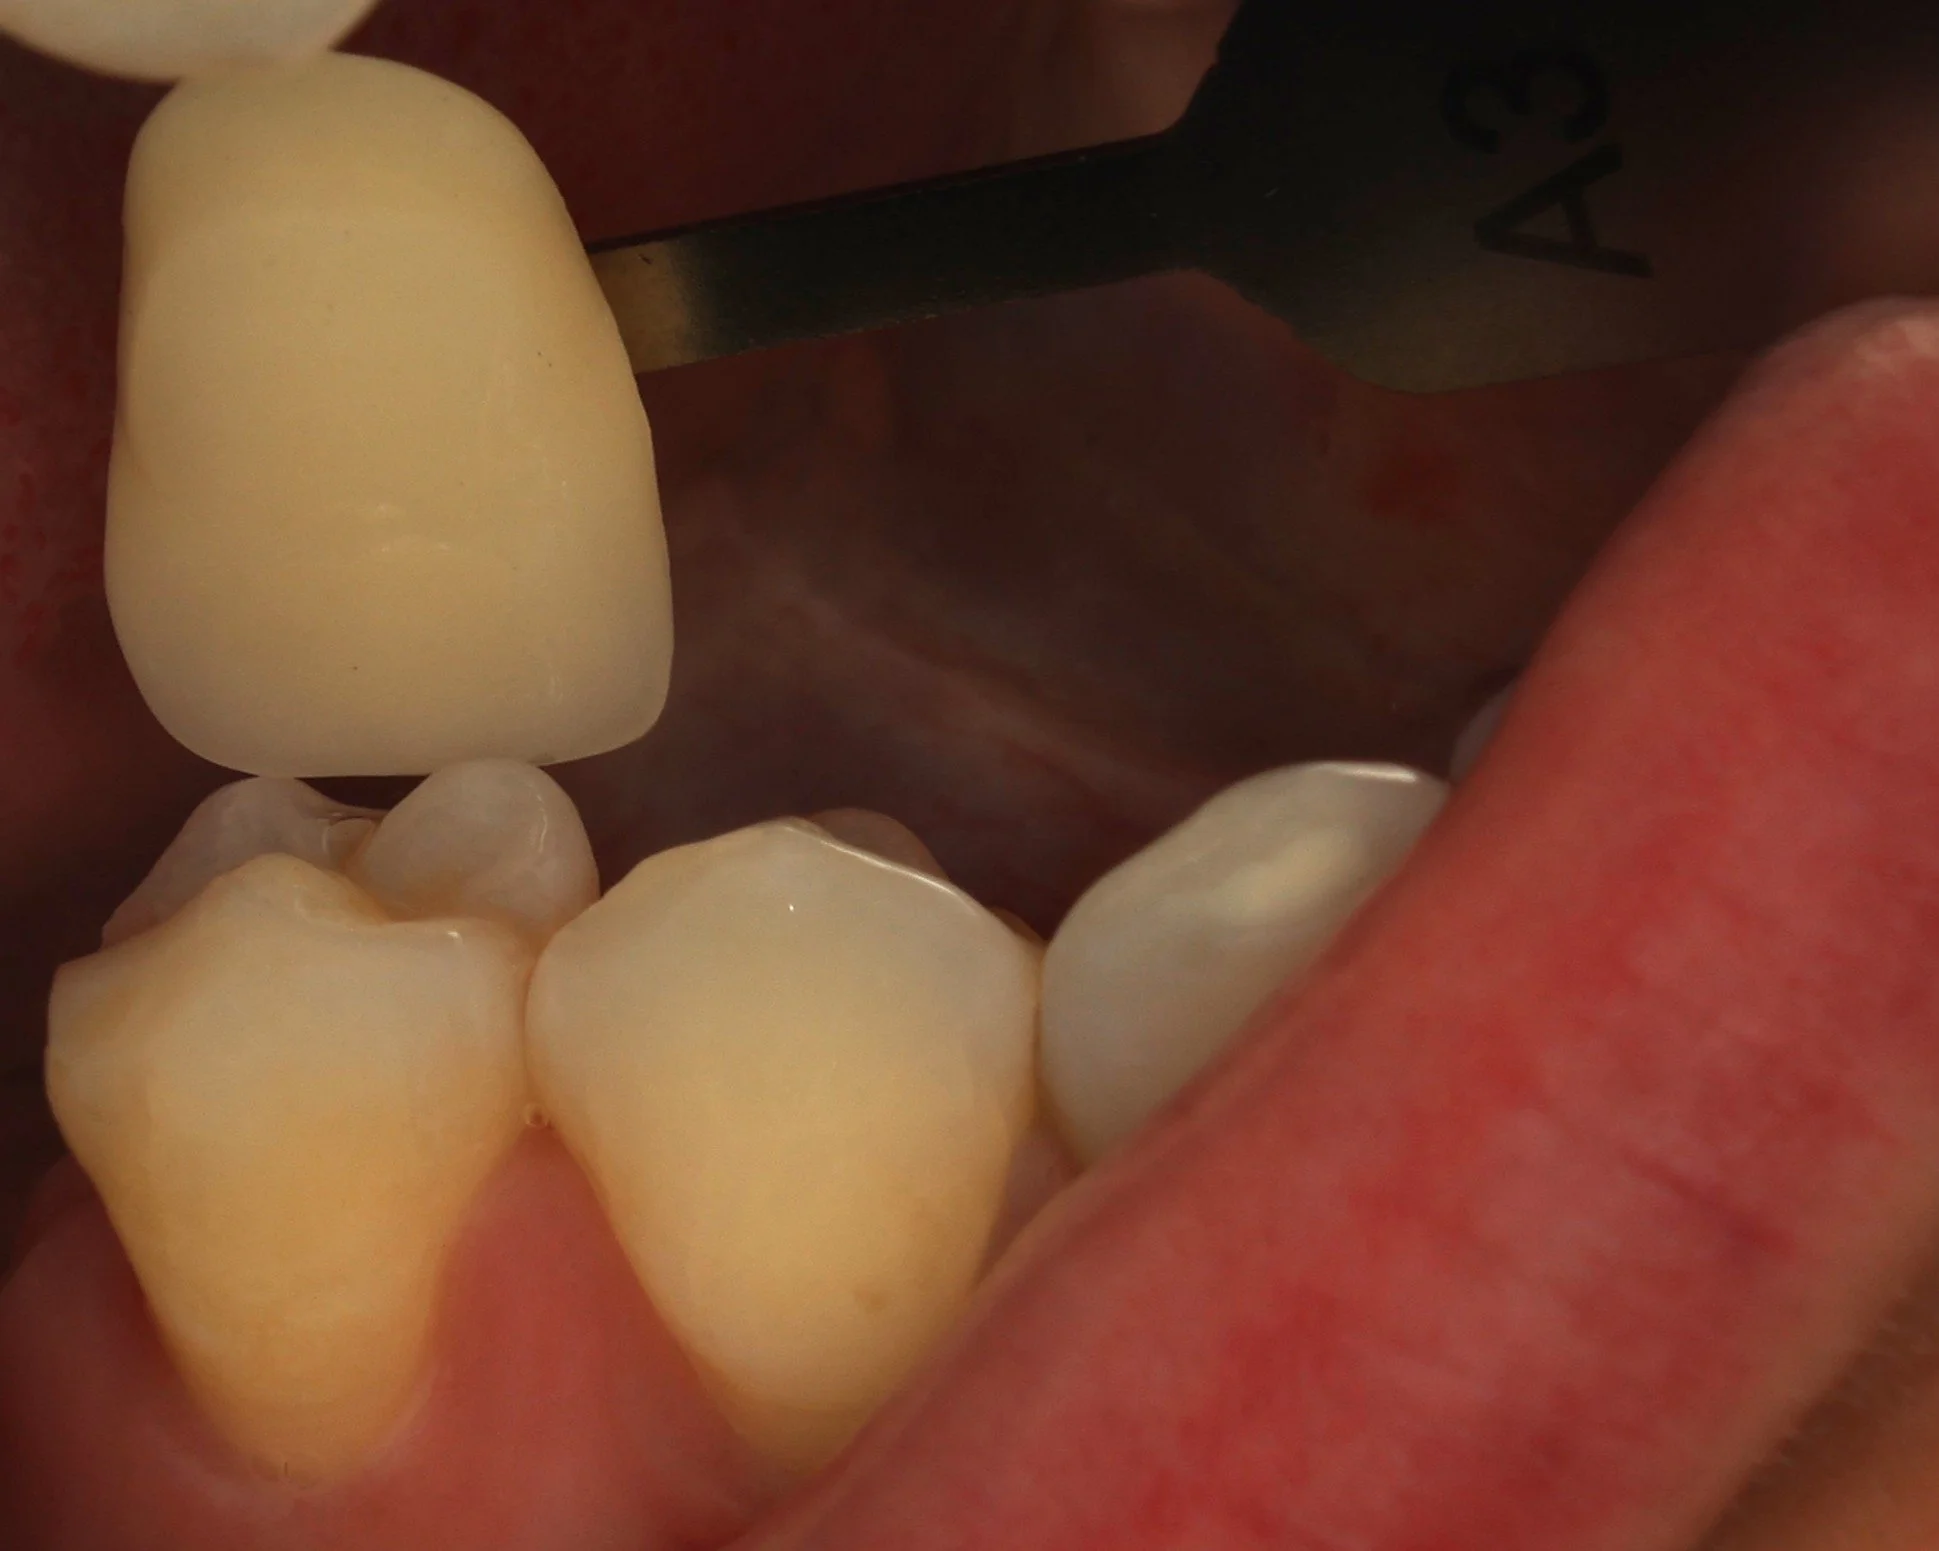

Relativement récents, les bridges collés cantilever postérieurs constituent une alternative fixe, fiable et véritablement minimalement invasive aux implants dans les secteurs postérieurs. Cette thérapeutique qui repose sur des indications bien précises est parfois débattue avec passion sur les réseaux sociaux ou dans les congrès scientifiques. Cependant des études cliniques existent, tout comme des recommandations validées dans des journaux internationaux. Leur succès repose sur des préparations et des principes biomécaniques rigoureux, pourtant simples à intégrer au quotidien. Cette intervention propose un guide clair et opérationnel incluant indications, étapes clés, protocoles d’adhésion et réglages occlusaux pour les mettre en œuvre avec confiance et reproductibilité.